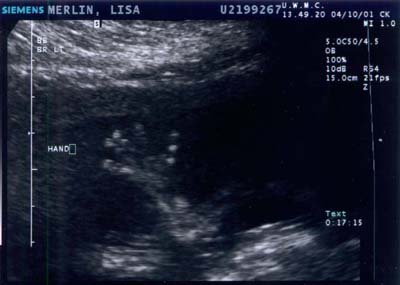

Baby A during ultrasound on 8 JUNE 2001 - Week

25

You might be able to make out the torso and leg. The baby is facing right.